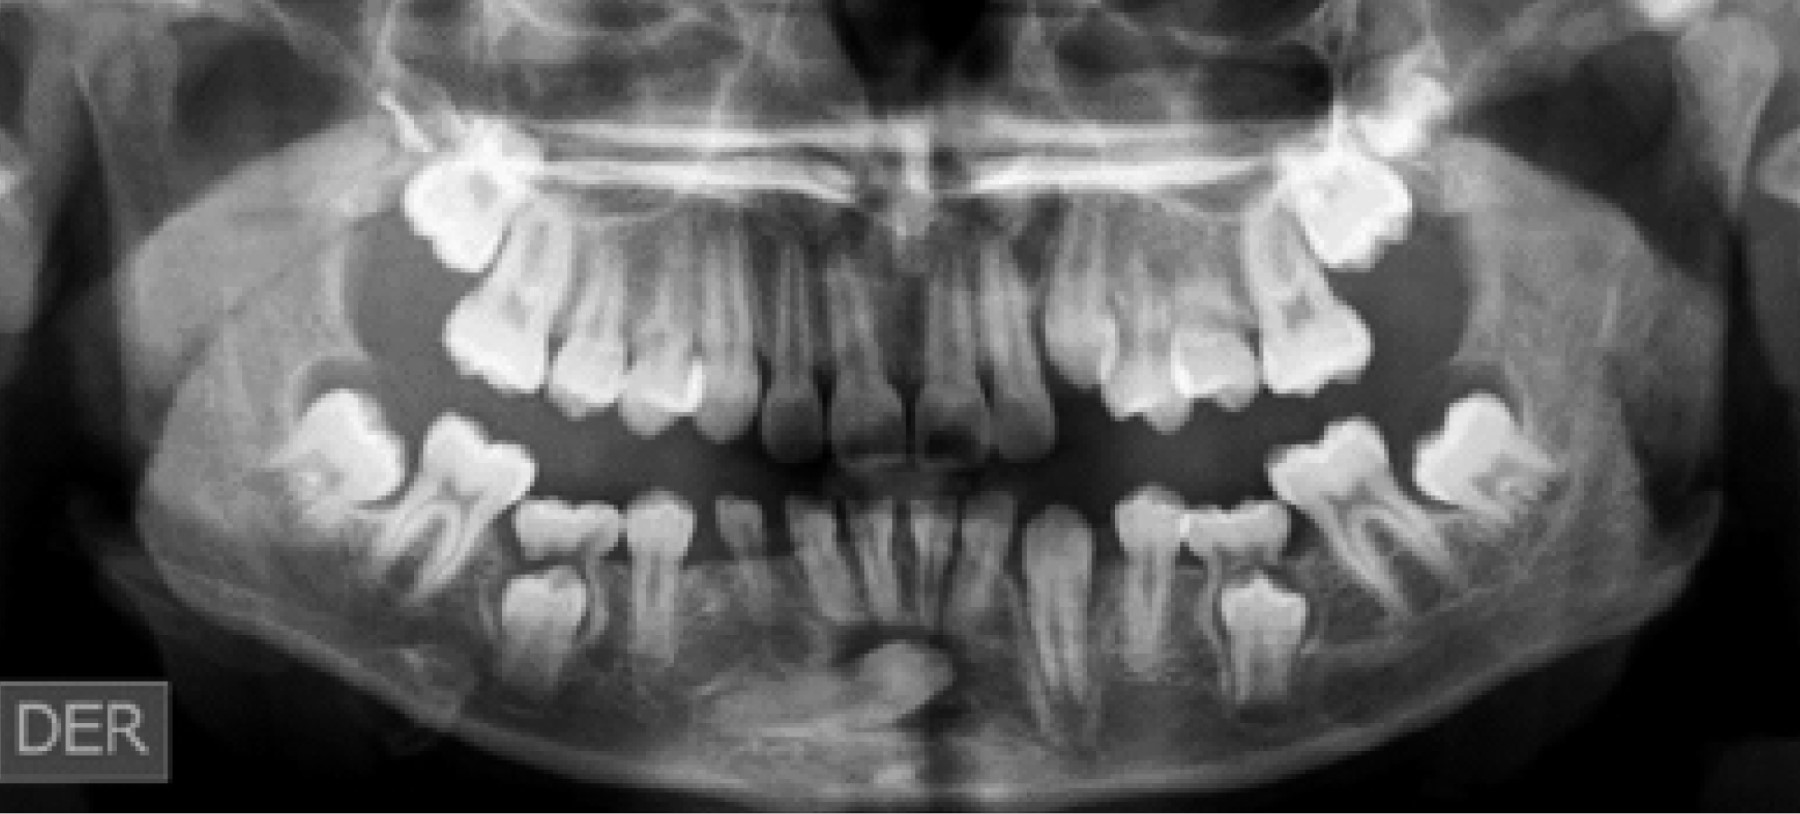

Se indica la exodoncia de la pieza; sin embargo, el paciente no acude a su cita quirúrgica. Un año después, en agosto de 2017, vuelve a acudir a la consulta y es derivado a toma de TCCB, donde se puede apreciar la disposición que adoptó el canino inferior transmigrado (Figura 4).

Figura 4